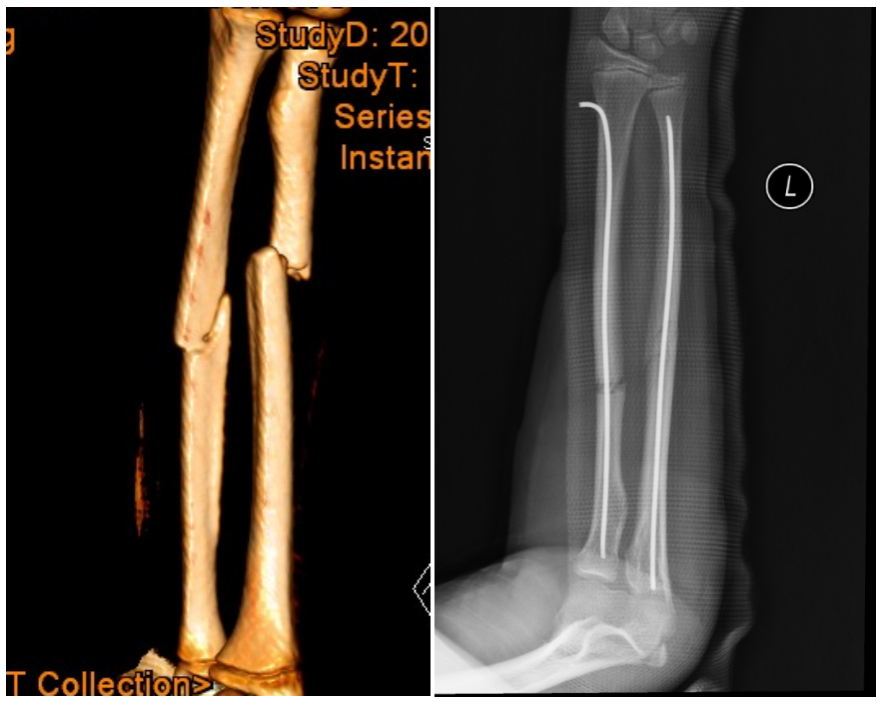

1.小儿骨折微创手术治疗:

治疗范围:儿童股骨骨折、胫腓骨骨折、肱骨骨折及尺桡骨骨折。

微创手术治疗:微创手术采用闭合复位,具有手术切口小、软组织损伤小、手术时间段、术后康复快、住院时间短及并发症少等优点,给早期锻炼和康复带来了条件和机会。

弹性髓内针治疗:是儿童长骨骨折的一种有效方法,具损伤小、不干扰骨折断端局部血运、不损伤骨骺、患肢功能恢复快及并发症少等优点。